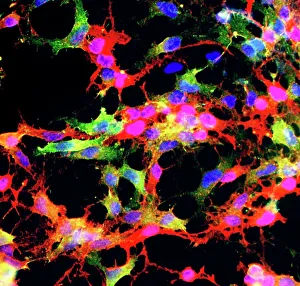

The central nervous system, the intricate network that governs our every thought and movement, is a marvel of complexity. From the delicate cerebellum tissue to the detailed light micrograph capturing its essence, we are reminded of its importance in maintaining balance and coordination. Anatomy comes alive as we explore the human brain from an inferior view. The intricacy of brain fibers is revealed through DTI MRI scans like C017/7099 and C017/7035, showcasing their vital role in transmitting information throughout this extraordinary organ. Artistic renderings bring us closer to understanding the medulla oblongata's significance within the brain. Its portrayal in various artworks allows us to appreciate how it controls essential functions such as breathing and heart rate. As we delve deeper into studying the central nervous system, models of the human brain provide invaluable insights into its structure and organization. Lateral views reveal countless regions responsible for cognition, emotion regulation, sensory perception, and motor control. Microscope slides offer glimpses into nerve cells' intricate architecture—a testament to their ability to transmit electrical signals at lightning speed. Meanwhile, glial stem cell cultures captured under a light microscope remind us of their crucial role in supporting neuronal function. Finally, artistic representations unveil the limbic system's enigmatic nature—an interconnected web responsible for emotions and memory formation. These captivating artworks allow us to visualize this complex network within our brains. Exploring these hints provides a glimpse into the awe-inspiring world of our central nervous system—the very foundation upon which our thoughts, actions, memories reside—reminding us just how remarkable our brains truly are.